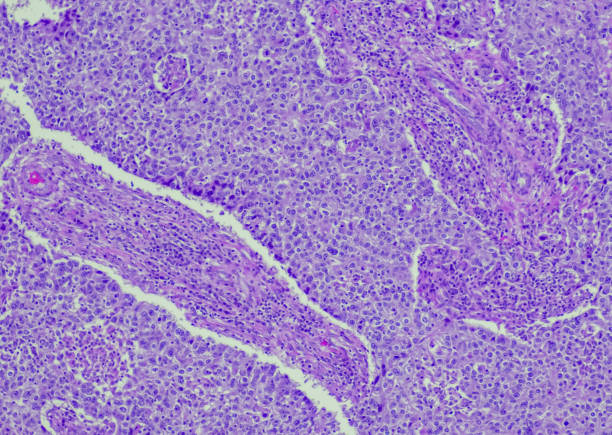

유방암 전조증상

유방암 전조증상으로 겨드랑이 멍울이 생기는 경우는 드물지만, 가능성이 있는 증상 중 하나입니다. 겨드랑이 멍울이나 종양은 유방암이 아닌 다른 병리적 상황에 의해서도 발생할 수 있습니다.

유방암 전조증상 중 하나인 겨드랑이 멍울이 생기는 이유는, 유방암 조직이 겨드랑이에 위치하고 있는 림프절을 침범하여 림프절에 암세포가 증식하면서 발생할 수 있습니다. 이런 경우 멍울은 보통 하나가 아니라 둘 이상 발생하며, 멍울이 커지거나 감소하지 않는 경우가 많습니다. 또한, 멍울을 누르거나 만지면 아픈 경우도 있습니다.